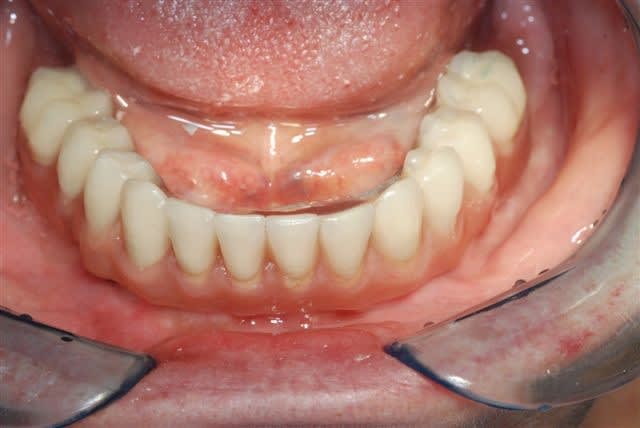

j'avais promis de montrer la suite et la fin du cas.

Alors voilà: empreinte pick-up mixte (silicone et plâtre snowhite), RIM avec cire calée sur des piliers hauts, et aujourd'hui retrait des implants provisoire et vissage de la prothèse.

Belle cicatrisation osseuse en distal de H1.

Obs : pas facile le passage des brossettes interdentaires pour la patiente !!

il se trouve que la parallélisme des implants était tel que j'ai pu me passer des piliers multi. L'empreinte au plâtre est sortie sans forcer et l'insertion ce matin à la pose s'est faite de même (je pensais à l'extrême limite devoir shorter un peu les bords des hexagones, mais même pas), juste au dessus des hexagones on a une liaison conique à 11°. Une prothèse est déjà réalisée tout en résine et incluant les piliers usinés, puis la résine est évidée en lingual, une maquette en cire est réalisée en épousant le plus possible les piliers. Elles est ensuite coulée, adaptée contre les piliers et enfin soudée au laser avec apport de cobalt conte les piliers....la passivité est conservée. Maintenant, c'est la première fois que je n'utilise pas les piliers multi, ici c'est assez par hasard que les implants aient été parallèles. c'est vrai que le coût en a été moindre mais ce n'était pas l'objectif premier.

pour le passage des brossettes, on a testé au labo et confirmé avec la patiente à la pose..çà passe et la patiente a compris le geste...(à vérifier cependant avec elle dans quelques jours)